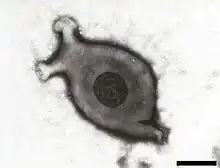

Electron micrograph of Mycoplasma gallisepticum, scale bar 140 nm